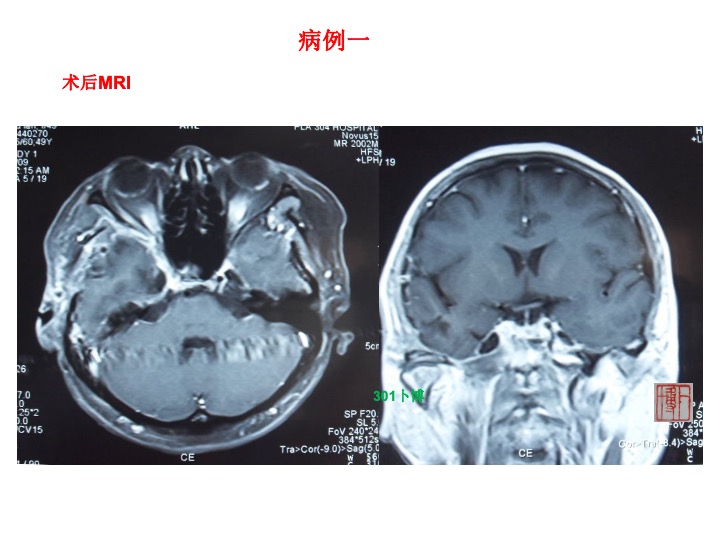

病例1,女性,49岁。主因头痛右侧面部麻木3个月入院。查体:右侧面部痛温觉减退,右侧咬肌轻度萎缩。CT提示中颅窝底骨质吸收破坏。MRI示中颅窝底鞍旁长T1长T2占位,可明显强化。部分肿瘤突入颞下窝。术后强化MRI提示肿瘤切除理想。